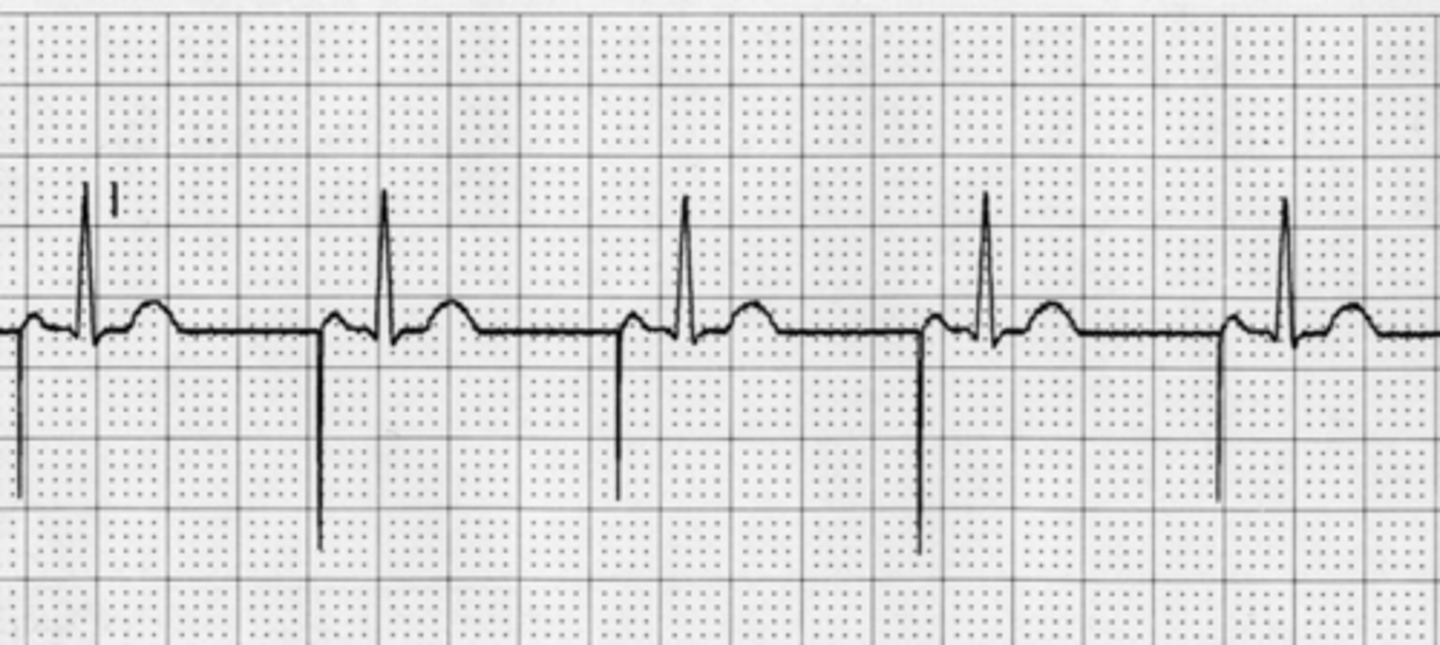

What is third degree heart block?

PR interval is regular but does not match up to QRS.

What is the treatment for third degree heart block?

pacemaker